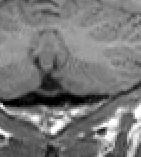

In the Sagittal view, locate the Obex on the Brainstem. Select the 'ignored contour' (e.g. the cyan color) and draw a horizontal line from this point to the anterior most part on the brainstem.

This line will appear as a cyan dot in the Coronal view and mark the inferior boundary of the brainstem.

Proceeding posteriorly, extract all Cerebellum and surrounding CSF. Take care to exclude the sinuses surrounding it.